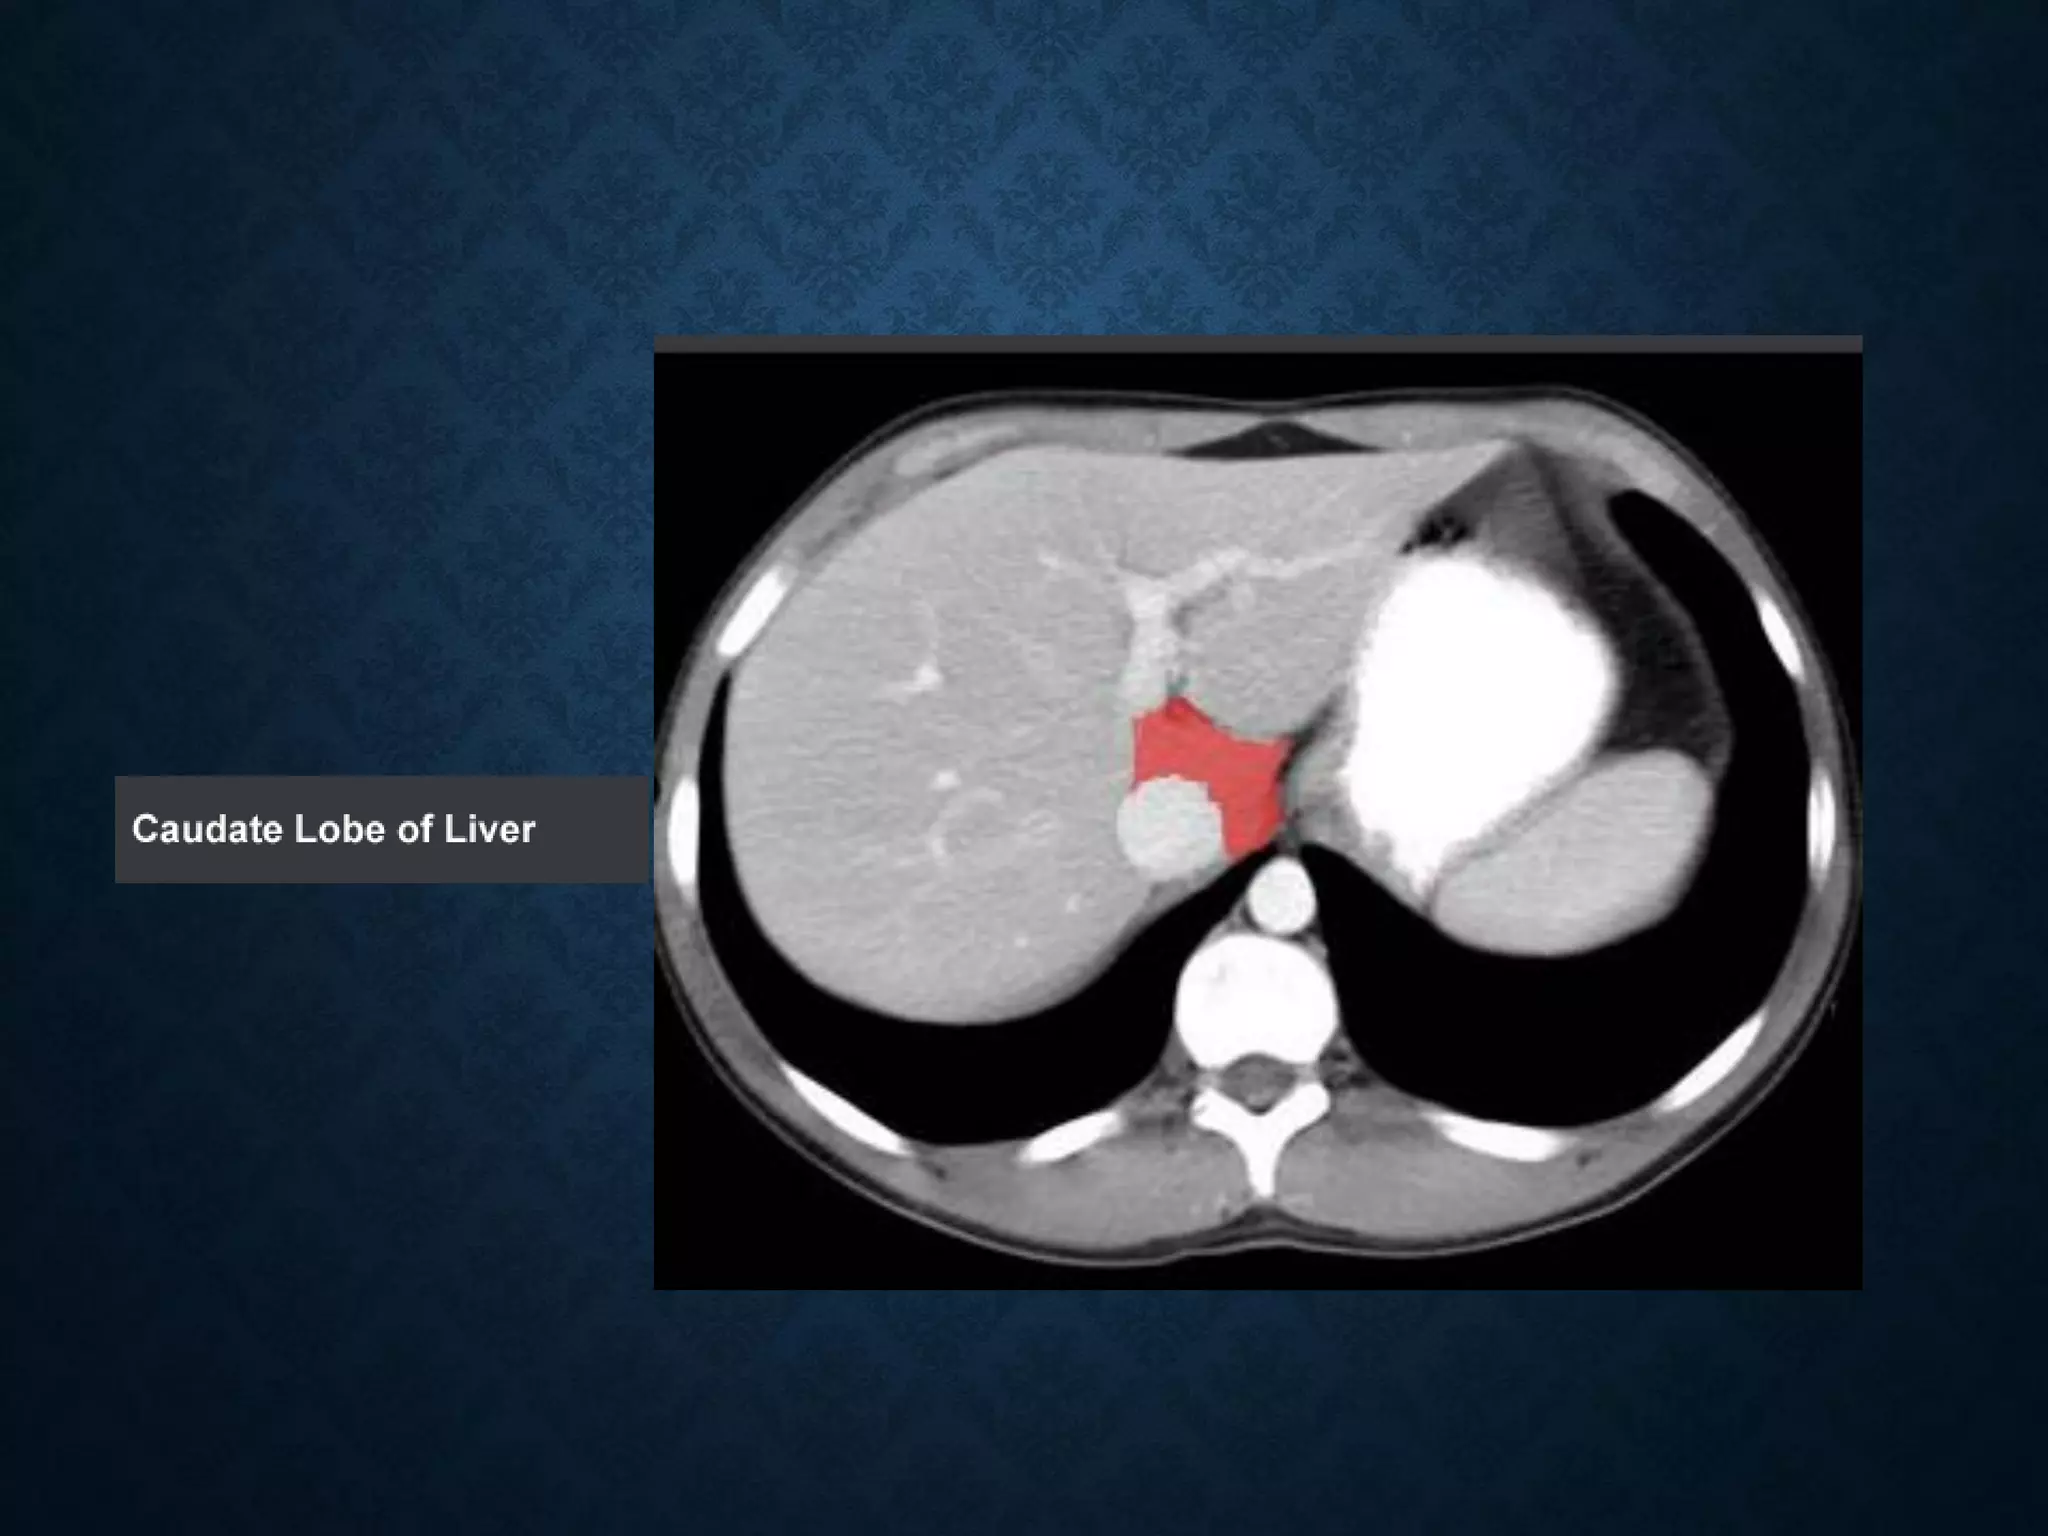

Identify the following structures in the body CT to the right. To view the location of the structure in the image click on

the label at the left and the structure will be indicated in the image. Abdominal CT scans typically begin just above

the diaphragm, so the first slice you see is of the lower chest.